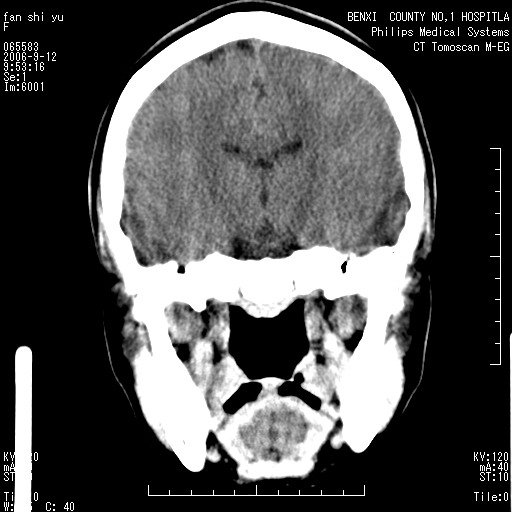

标题: CT4607:看看这个头颅冠状位。

女,22岁,自觉头顶部质硬包块.

巨大蛛网膜粒压迹。

巨大蛛网膜粒压迹